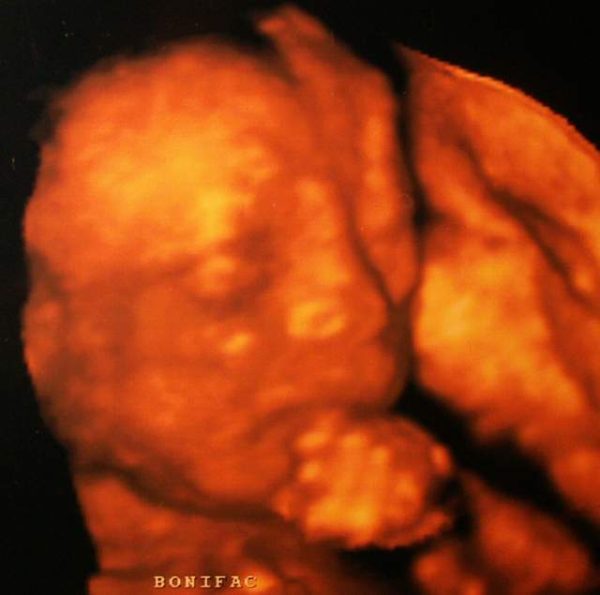

Tegnap voltunk aztán Kecskeméten 4d-n, amit a saját dokim is javasolt. Ott nagyon alaposan megnézte a doki a babát, azért is mert ugye 40 elmúltam. Mindent rendben lévőnek látott a kisfiunknál. Aztán kérésemre még egyszer alaposan megnézte a beleket, amin ugye 18 hetesen eltérést látott a doki. Tüzetesen átnézte, elmagyarázta mit láthattak, de most teljesen rendben van.

Itt van a mi gyönyörűségünk: Kép

Stella örülök hogy végre itt vagy nagyon jó a kép tényleg szép az arca :wink: Gyere egy kicsit sűrűbben !!

Bonifác gyönyörű és főként egészséges baba!